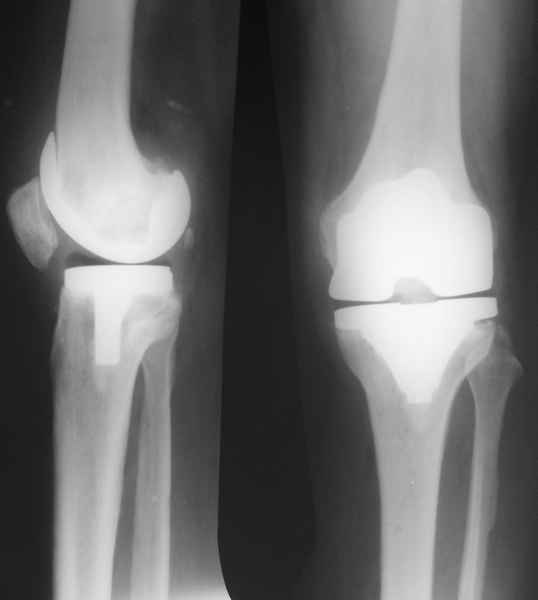

В феврале 2007 года пациентке выполнено эндопротезирование коленного сустава.

13/02/07

25/07/07

дек. 07

25/06/08

14/01/09

Через 1 месяц после операции объем движений 90 градусов, через 2 месяца 60, через 3 - 40, через 5 - качательные движения.

В июле 2007 года выполнена ревизия - полости сустава нет. Капсула сустава имеет толщину от 1 до 1.5 см, собственная связка надколенника имеет толщину до 3 см. Сустав заполнен фиброзно-рубцовой тканью. Компоненты стабильны.

Скорее всего тибиальное плато было не конца резецировано и в задненаружных отделах осталась ступенька. Это привело к тому, что тибиальный компонент завалился на варус.